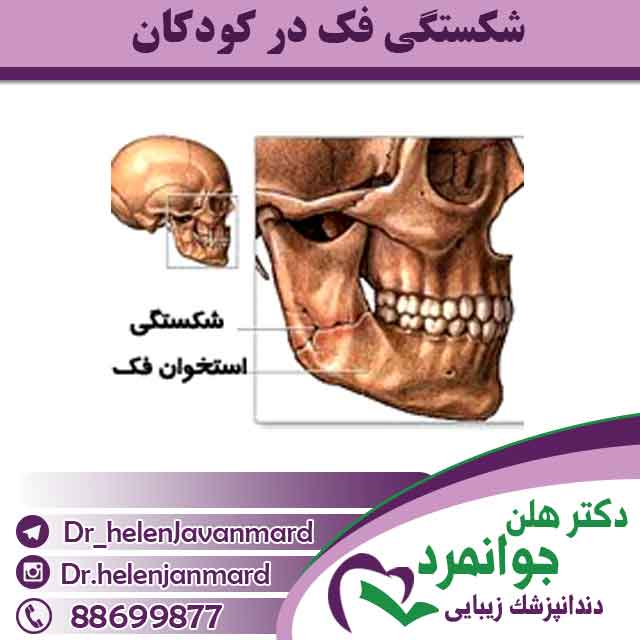

شکستگی فک در کودکان

شکستگی فک در کودکان در محدوده سنی پایین 5 سال بیشتر از بزرگسالان دیده می شود .بیشتر شکستگی ها در کودکان در استخوان فک پایین...